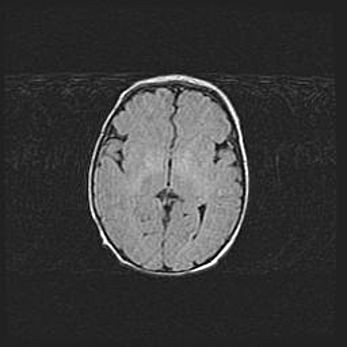

Наружная гидроцефалия с возможной атрофией височных областей.

Возраст: 28 дней

Вес: 3670 г

Пол: мужской

Окружность головы: 38 см

Срок гестации: 40 недель

Гидроцефалия головного мозга у новорожденных – это заболевание, которое характеризуется скоплением избыточного количества спинномозговой жидкости в желудочковой системе головного мозга в результате затруднения её перемещения от места выработки к месту поглощения в кровеносную систему или вследствие нарушения абсорбции. При открытой наружной форме гидроцефалии у новорожденных расширяются и переполняются субарахноидные пространства.

При нормотензивных  формах,  которые,  как  правило,  являются  следствием  перенесенных ишемических  повреждений  паренхимы  мозга,  возможно  сочетание микроцефалии  с нормотензивной гидроцефалией. В основе данных изменений лежит атрофия больших полушарий с преимущественной  локализацией  в  лобно-височных  областях.